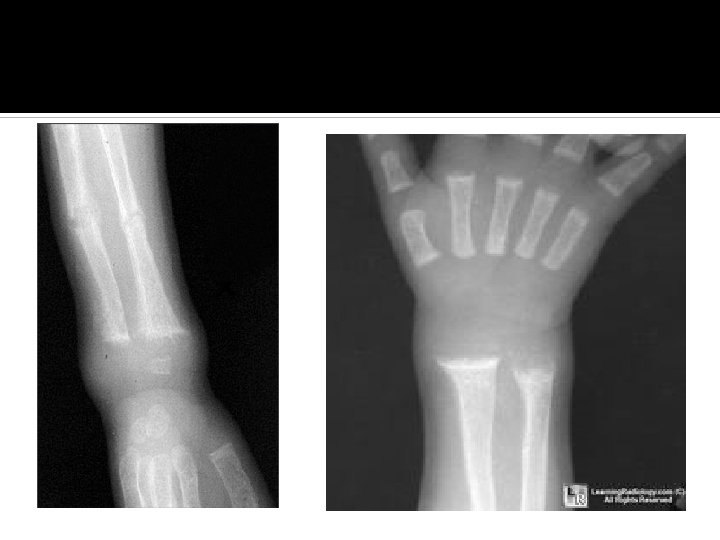

Rickets confirmed if: Low or normal serum Ca Low phosphorus High alkaline phosphatase X rays of ends of long bones at knees or wrists: Widening, fraying, cupping of the distal ends of the shaft. Vit D level low Parathyroid hormone high

Rickets: Effects on growth plate Inadequate growth plate mineralization. Defective calcification in the interstitial regions Increase in thickness of growth plate. The columns of cartilage cells are disorganized.

Skeletal and Radiographic Findings Associated with Rickets Bowing or widening of physis Costochondral beading (rachitic rosary) Craniotabes Delayed closure of anterior fontanel Dental abnormalities Flaring of ribs at diaphragm level (Harrison’s groove) Flaring of wrists Fraying and cupping